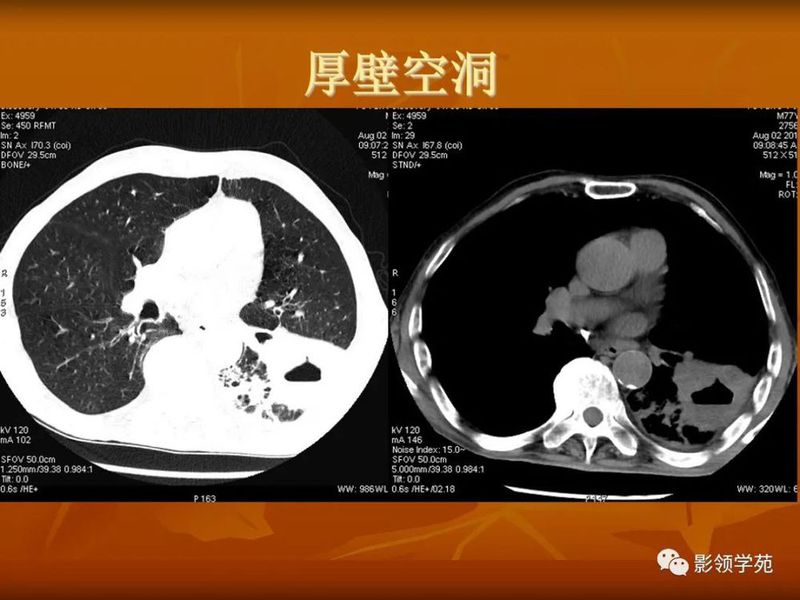

(1)较大含空洞性肿块,洞壁较厚,大于15mm,空洞外壁有分叶、毛刺,洞壁凹凸不平有壁结节,增强可见不规则强化,周围未见明显卫星病灶时,首先考虑周围型肺癌;癌性空洞洞壁一般肺门侧较厚,空洞多偏于外侧,伴有同侧淋巴结肿大更支持肺癌诊断。

(2)空洞病变发生于双肺上叶尖后段、下叶背段,病变周围可见点状、结节状及片状卫星病灶,洞壁组织无明显强化或有包膜线样强化时,考虑结核;结核球的空洞多位于病变的肺门侧,与引流支气管相同,洞内壁一般较光滑。